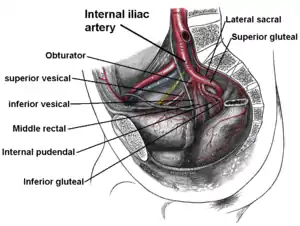

Blood and lymphatic vessels

The prostate receives blood through the inferior vesical artery, internal pudendal artery, and middle rectal arteries. These vessels enter the prostate on its outer posterior surface where it meets the bladder, and travel forward to the apex of the prostate.[3] Both the inferior vesicle and the middle rectal arteries often arise together directly from the internal iliac arteries. On entering the bladder, the inferior vesical artery splits into a urethral branch, supplying the urethral prostate; and a capsular branch, which travels around the capsule and has smaller branches which perforate into the prostate.[3]

Imaging showing the inferior vesical, inferior pudendal and middle rectal arteries arising from the internal iliac arteries.

Imaging showing the inferior vesical, inferior pudendal and middle rectal arteries arising from the internal iliac arteries. Image showing the external iliac lymph nodes and their positions around the external iliac artery and vein